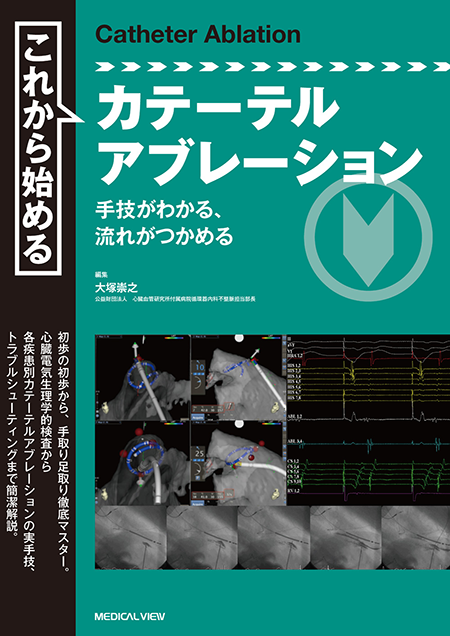

ziostation2を用いて心臓MRI検査の総合的な画像解析を可能にEVTテクニック これは困ったどうしよう/南都伸介(著者),飯田修(著者)